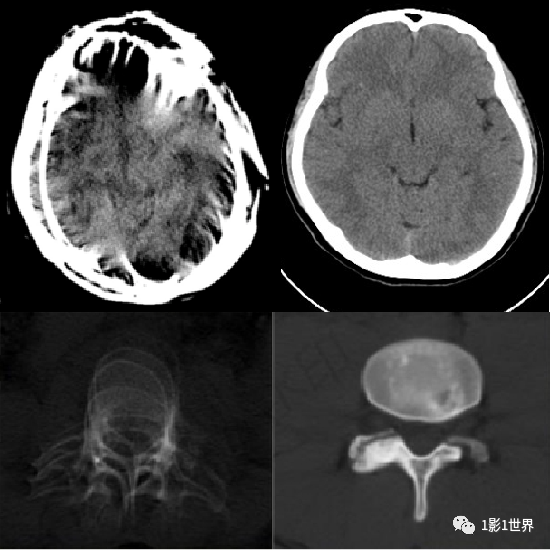

![]()

肺动脉CTA扫描:轴位CT图像显示上腔静脉、升主动脉和降主动脉造影剂强化,而肺动脉主干相对密度较低。

这种伪影可导致不确定的检查结果或被误解为肺栓塞